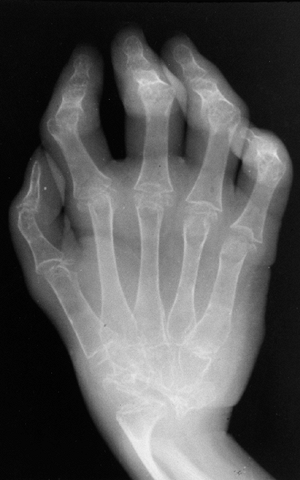

![]() |

Figure 12.2 Reflex sympathetic dystrophy in a child with a 1-month history of hand swelling and pain. A: Right hand after 1 month of illness. B:

Technetium 99 m bone scan showing diffuse increase in uptake of isotope in the affected hand. In some patients, isotope uptake is diffusely decreased. C: Right hand after 3 weeks of physical therapy and psychotherapy. |